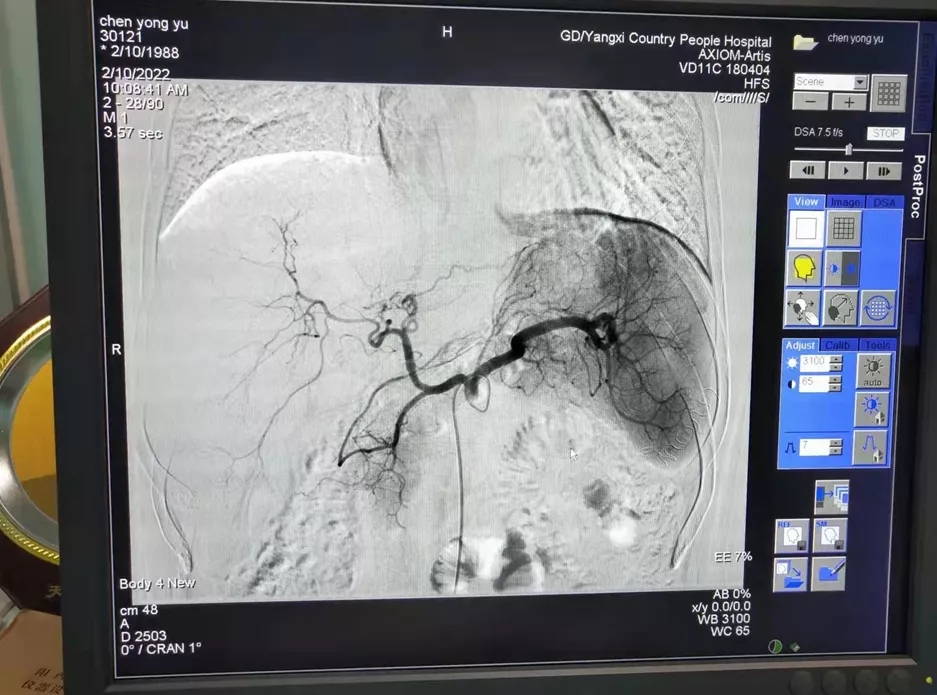

阳西总医院人民医院肿瘤科成功为患者进行了肝动脉灌注化疗(HAIC)。HAIC疗法经股动脉将微导管置于肝肿瘤分支血管,通过微导管将抗肿瘤药物直接送达肝内肿瘤血管达到治疗目的。经过1个周期的治疗,患者肝部肿瘤较前明显缩小,对胃的压迫减轻,已能正常进食,腹痛腹胀消失,再经过2个周期的HAIC治疗后,肝内巨大肿瘤染色基本消退。